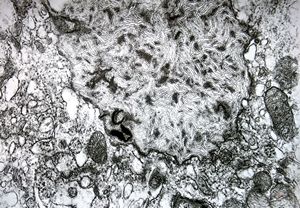

Whipple disease